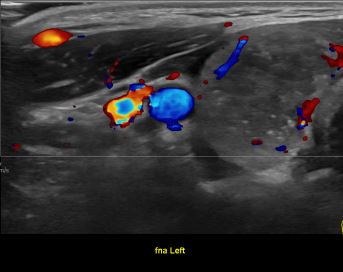

상기환자 좌측목 멍우리 있어 검사위해 내원하신 40대초반 여성분으로

의심스러운 갑상선 좌엽결절 세포검사 진행후 갑상선암으로 진단되었습니다